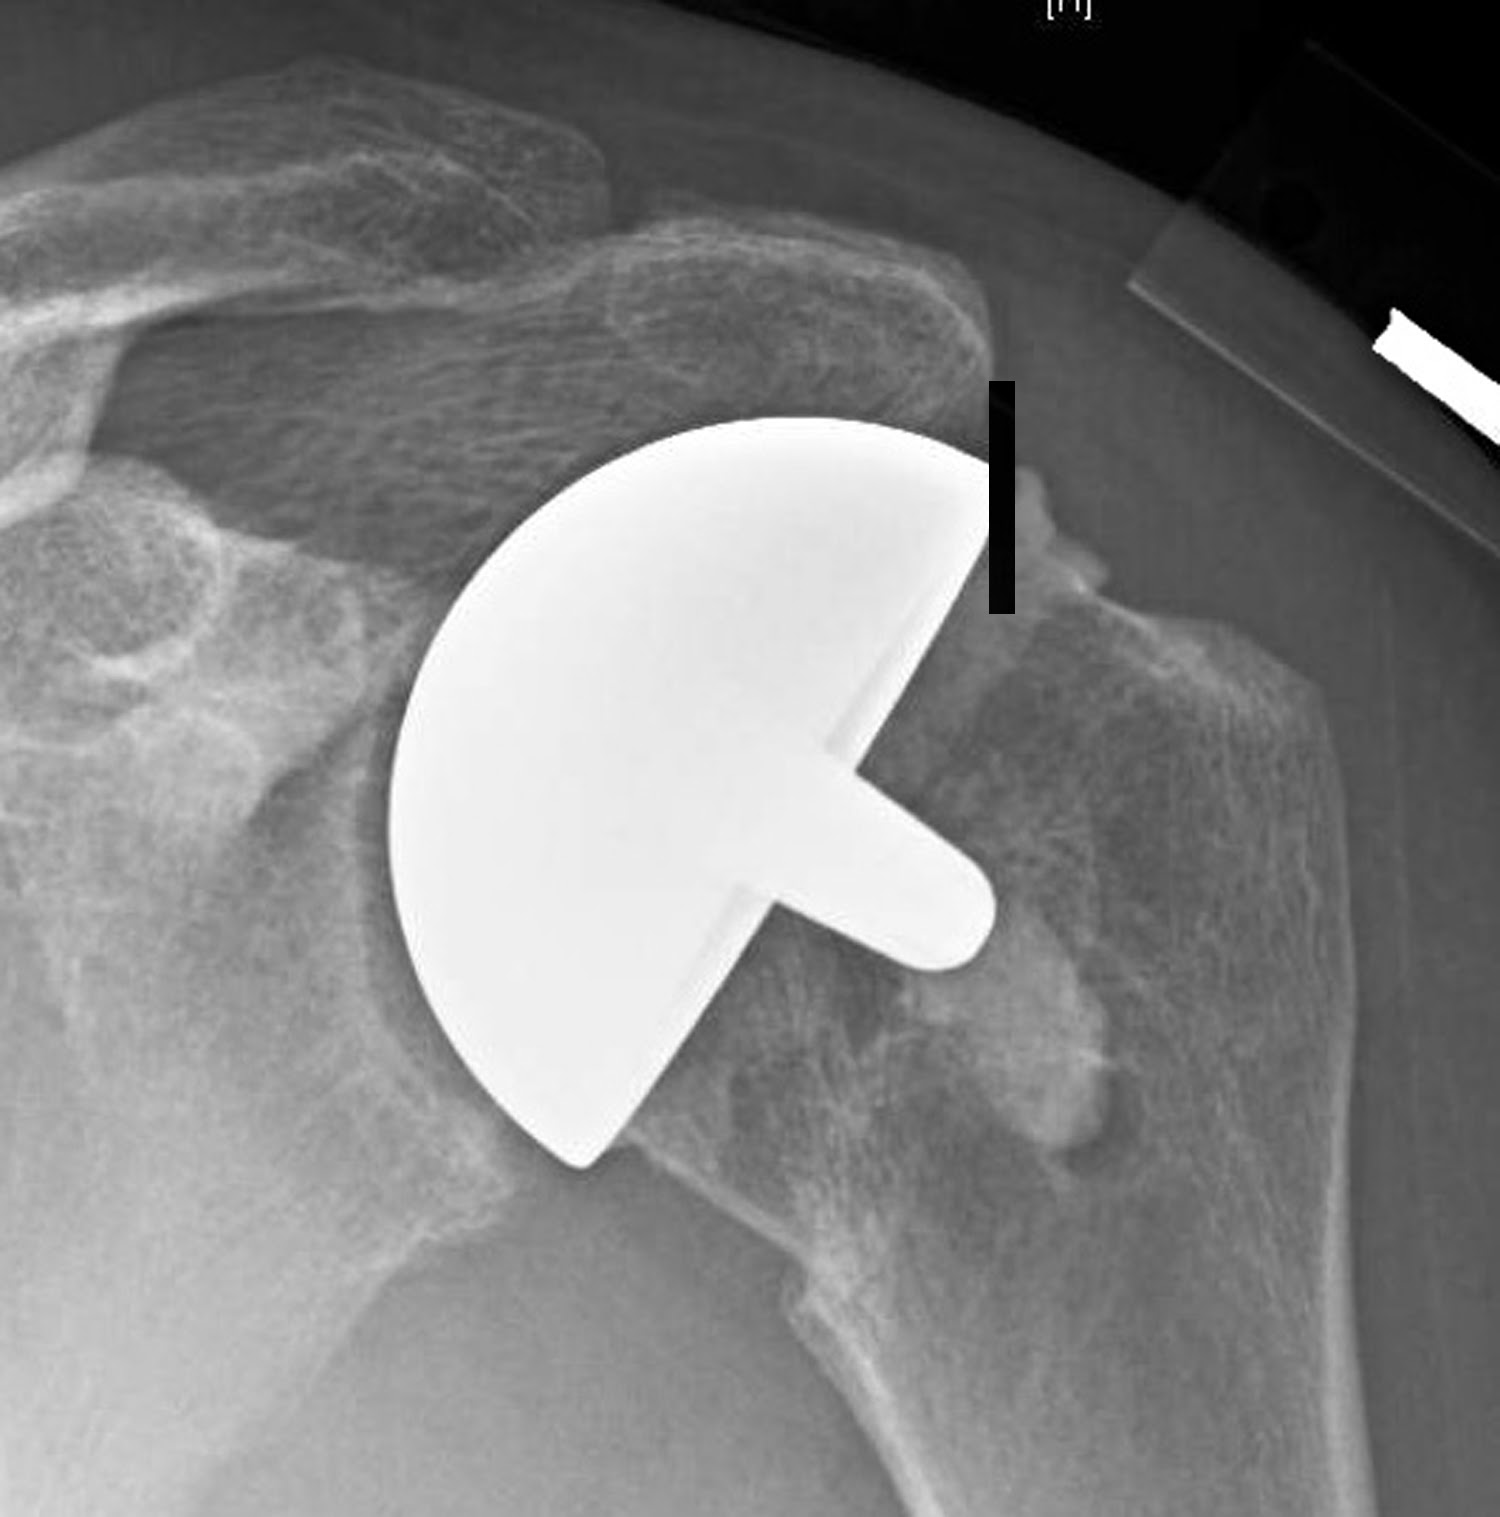

Film X ray shoulder show shoulder joint prosthesis. The patient has What Is A Partial Shoulder Replacement Only the ball gets replaced. Usually, you'd get this if you have. In others, the bone in the socket is too worn out. What is partial shoulder replacement? Partial shoulder replacement, also known as hemiarthroplasty, involves replacing only the. This surgery involves just the partial replacement of the injured shoulder’s parts. A shoulder replacement is a procedure that tries to. What Is A Partial Shoulder Replacement.